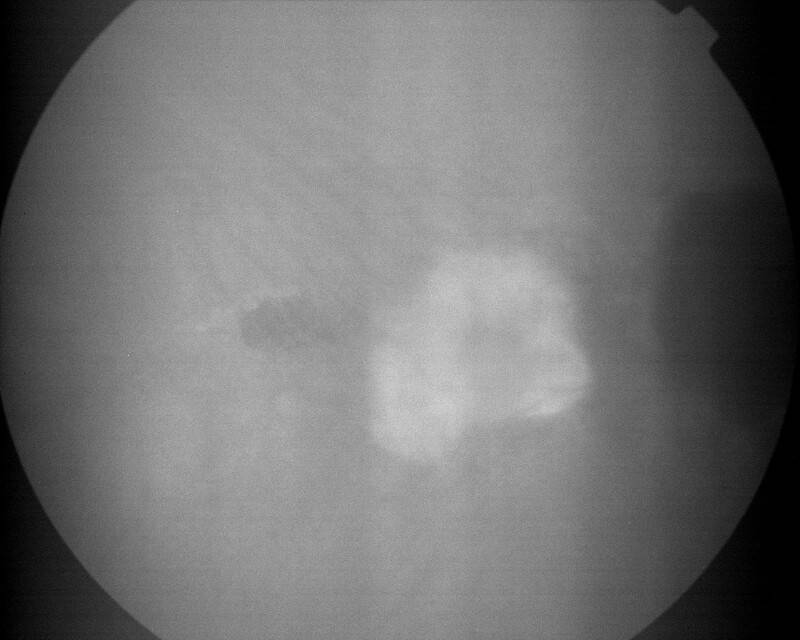

IMG0019.jpg